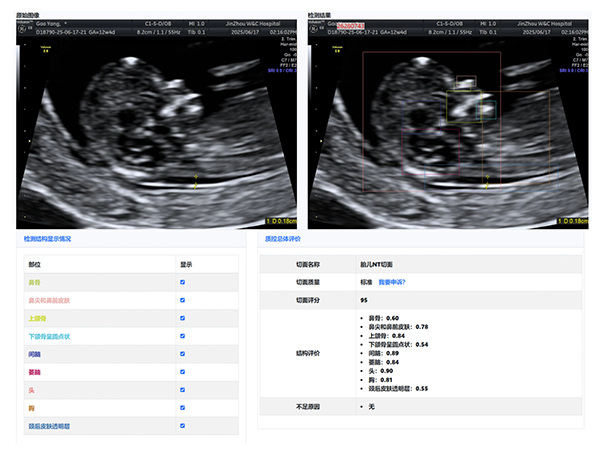

大赛汇聚了超声科全体医生,他们在产科超声领域各展所长。本次大赛引入了产前超声AI智慧云平台作为评分系统。

该平台利用先进的图像识别技术,对参赛的NT、I级、Ⅱ级、Ⅲ级产科超声图像进行精准分析与评分,确保了比赛的公正性与准确性,也体现了医院在医疗领域智能化、精准化的探索与进步。

经过激烈的角逐,年轻医生陈昱在NT产科超声图像评比中,凭借对NT精准的测量荣获第一名,展现出新生力量的专业风采;王斌医生在I级产科超声图像评比中,以精湛技术和对细节的精准把握摘得桂冠;刘芳医生的Ⅱ级产科超声图像作品,凭借清晰的图像质量和准确的诊断信息脱颖而出;Ⅲ级产科超声图像作品的评比竞争尤为激烈,李杭医生以微弱优势获得第一名。